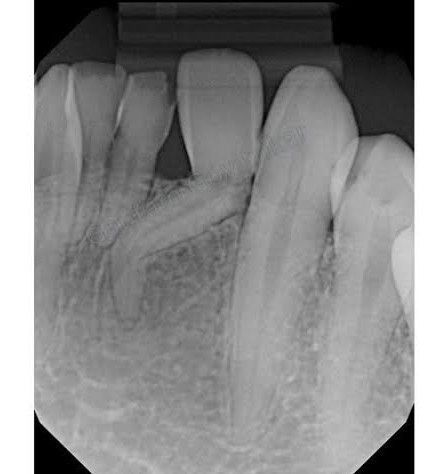

Two possible causes of dilaceration are trauma and developmental disturbances, and it has also been proposed that it might be associated with some developmental syndromes. Dilaceration can be seen in both the permanent and deciduous dentitions, and it is more commonly found in posterior teeth and in the maxilla.